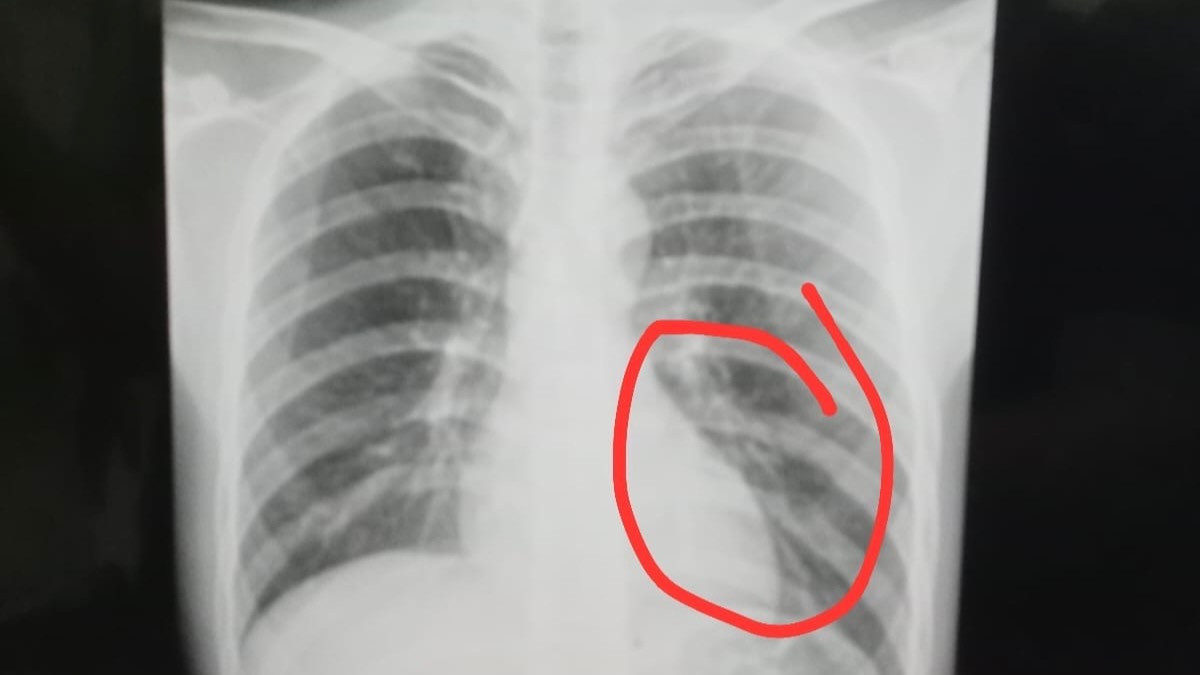

Hasil pemeriksaan rontgen menunjukkan adanya retakan pada tulang rusuk bagian bawah, yang menempatkan cedera Firman dalam kategori serius dan berpotensi berbahaya bila tidak ditangani secara optimal.

“Hasil pemeriksaan rontgen menunjukkan adanya retakan pada tulang rusuk bagian bawah. Kondisi ini masuk kategori cedera serius dan berisiko,” ungkap Rudi.